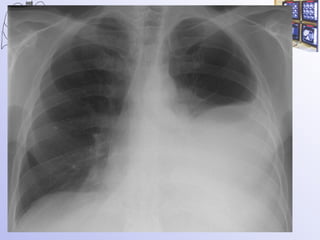

Рак легкого  в молодом возрасте